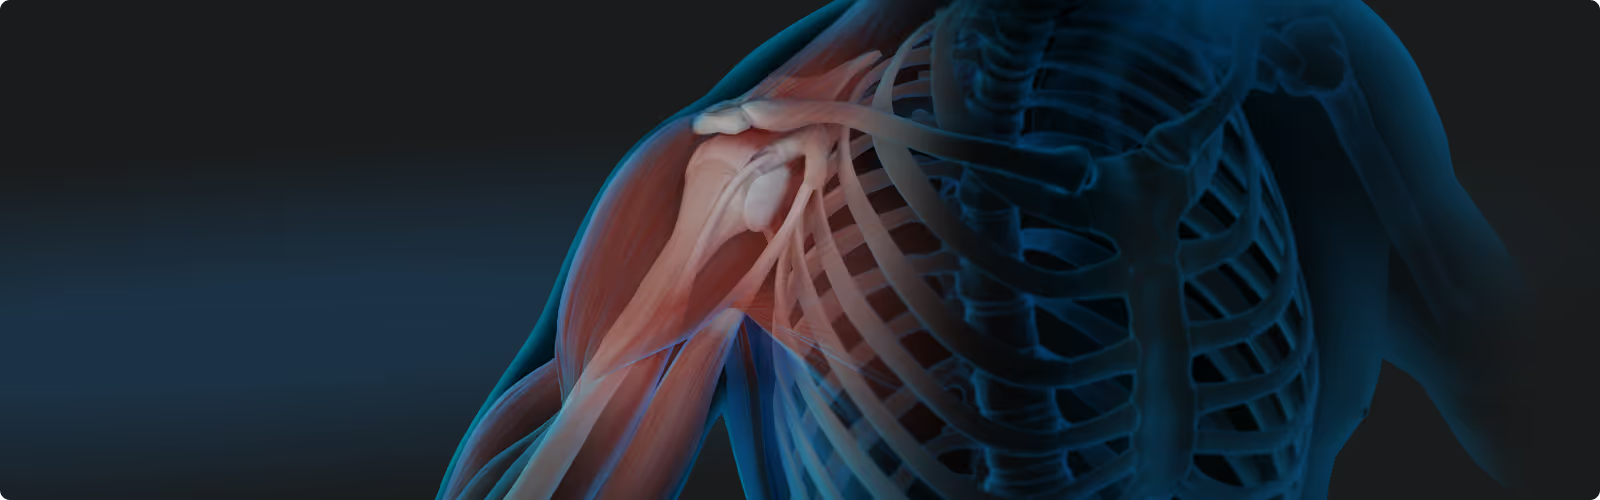

Select your application area and learn how to support your patients' recovery at the cellular level: